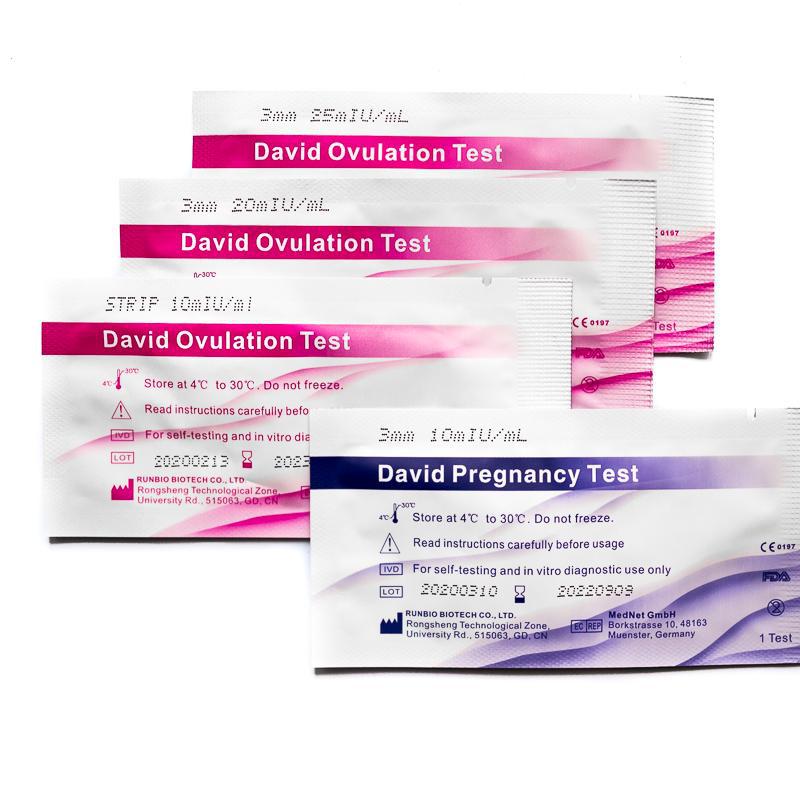

Je früher getestet wird, desto sensibler sollte der Schwangerschaftstest sein. Ein Schwangerschaftsfrühtest kann hCG bereits ab einer Konzentration von 10 mlU/ml erkennen, ein klassischer Schwangerschaftstest schlägt erst bei 20 mlU/ml an. Tests, die vor der ausbleibenden Periode durchgeführt werden, sollten immer eine geringere Sensitivität aufweisen.